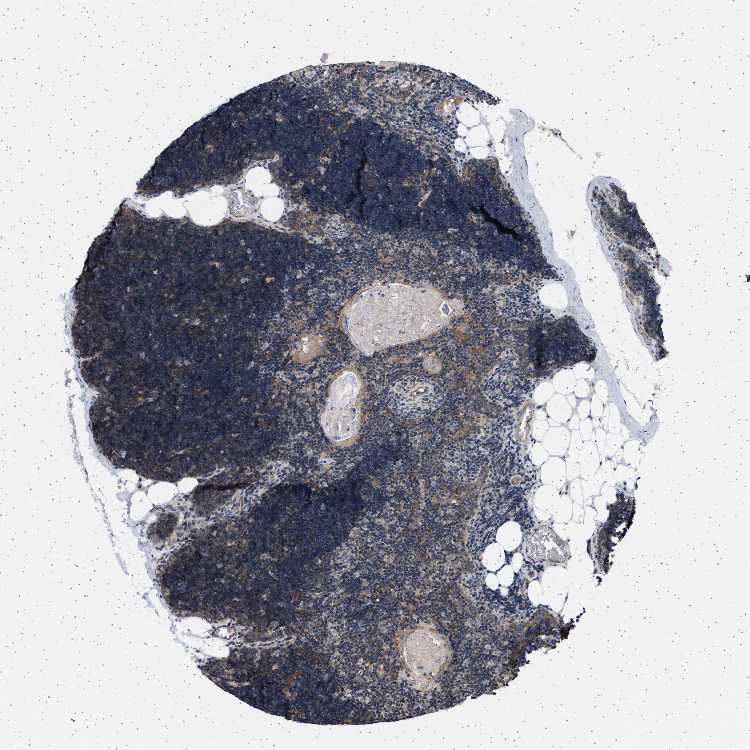

LYMPH NODE - HPA RNA-seqi

The RNA-seq details section shows detailed information about the individual samples used for the transcript profiling and results of the RNA-seq analysis.

Information about each individual sample is listed below, including gender, age, a tissue section image and estimated fractions of cell types. nTPM (normalized transcripts per million) values give a quantification of the gene abundance which is comparable between different genes and samples.

Average nTPMi

Max subtype nTPM is the value for the subtype with the largest average nTPM across the subtype samples.

8.0

overview

Male, age 34

Lymph node sample 173

nTPM: 5.6

Cell types%

Lymphocytes:

85

Other cell types:

15

Female, age 29

Lymph node sample 174

nTPM: 14.6

95

5

Female, age 61

Lymph node sample 175

nTPM: 5.7

Female, age 83

Lymph node sample 176

nTPM: 7.4

Female, age 52

Lymph node sample 177

nTPM: 7